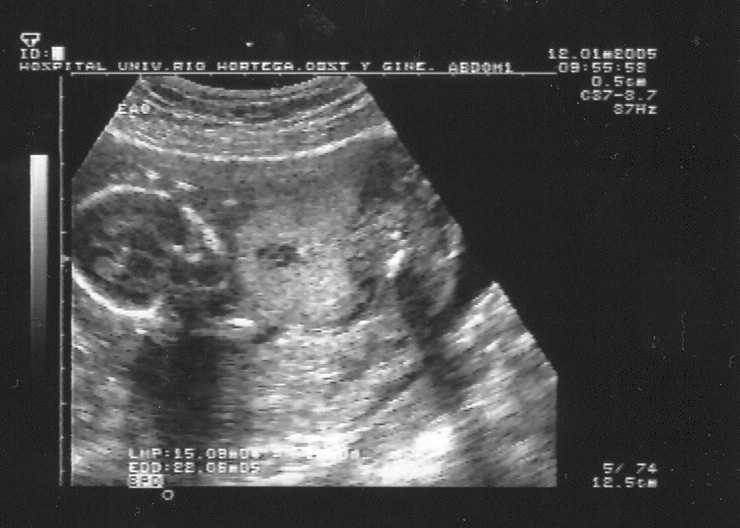

Atendemos a una mujer secundigesta, de raza eslava y de 30 años de edad, con antecedente de gestación anterior inviable, por una agenesia renal bilateral, y DAQP, detectada en la necropsia. La paciente es remitida a nuestro servicio para la realización de amniocentesis genética, que se lleva a cabo en la semana 15, apreciándose una incipiente displasia adenomatoide quística tipo III, así como un oligoamnios moderado. Se citó a la paciente para la semana 17 de edad gestacional, cuando se apreció una displasia adenomatoide quística tipo III que ocupaba todo el tórax, desplazando al corazón y afectando a los 2 pulmones (fig. 1). Se observó además una incipiente hidropesía fetal con hidrotórax y ascitis (fig. 2). Este hecho contrastaba con el grave oligoamnios y la agenesia renal bilateral con ausencia de llenado vesical (fig. 3). El estudio del cariotipo resultó normal y la paciente decidió realizar la interrupción voluntaria del embarazo en su centro de origen.

Figura 3. Oligoamnios severo y agenesia renal bilateral.